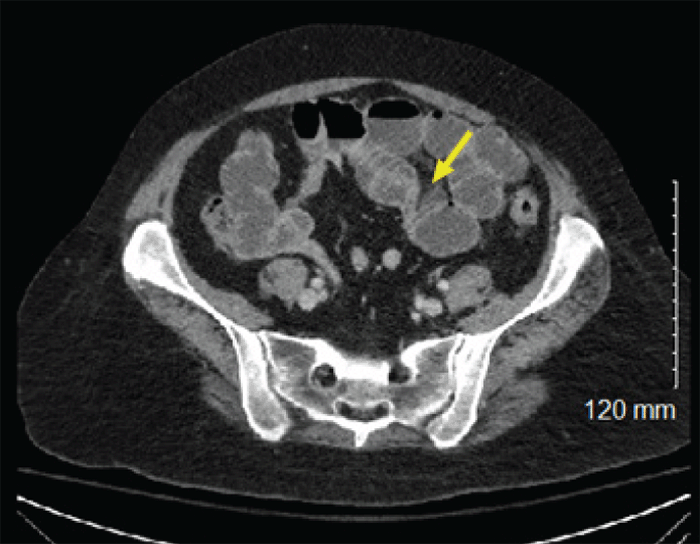

Her abdomen was soft, distended, tympanitic, nontender, with no notable hernias or scars on physical exam. Her lungs were clear to auscultation bilaterally, and there was no lymphadenopathy noted. Her right lower extremity was in a brace, and her hands were described as "agitated." ED labs were significant for WBC 19000 and slight hyponatremia of 134. Computed tomography (CT) of the abdomen and pelvis showed a partial bowel obstruction with a transition zone in the left hemiabdomen but no clear transition point (Figure 1). The distal small bowel was decompressed with no evidence of bowel ischemia or perforation. She was also noted to have nodular opacities at the bilateral lung bases (Figure 2).

Figure 1. Axial CT Abdomen and Pelvis with Contrast Showing Dilated Loops of Small Bowel With Transition Zone in Mid-abdomen. Published with Permission